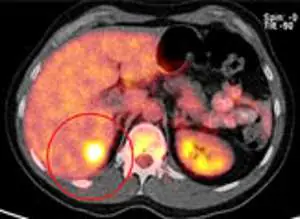

Лечение метастаза рака кишечника в печени кибер-ножом

МРТ-исследование метастаза рака кишечника в печень

На ПЭТ-КТ выявляется биологическая активность в центре опухоли

МРТ печени через 8 недель после лечения. Терапия была проведена под контролем фаз дыхания Киберножом. Опухоль разрушена, центральный некроз, реакция окружающих тканей минимальна